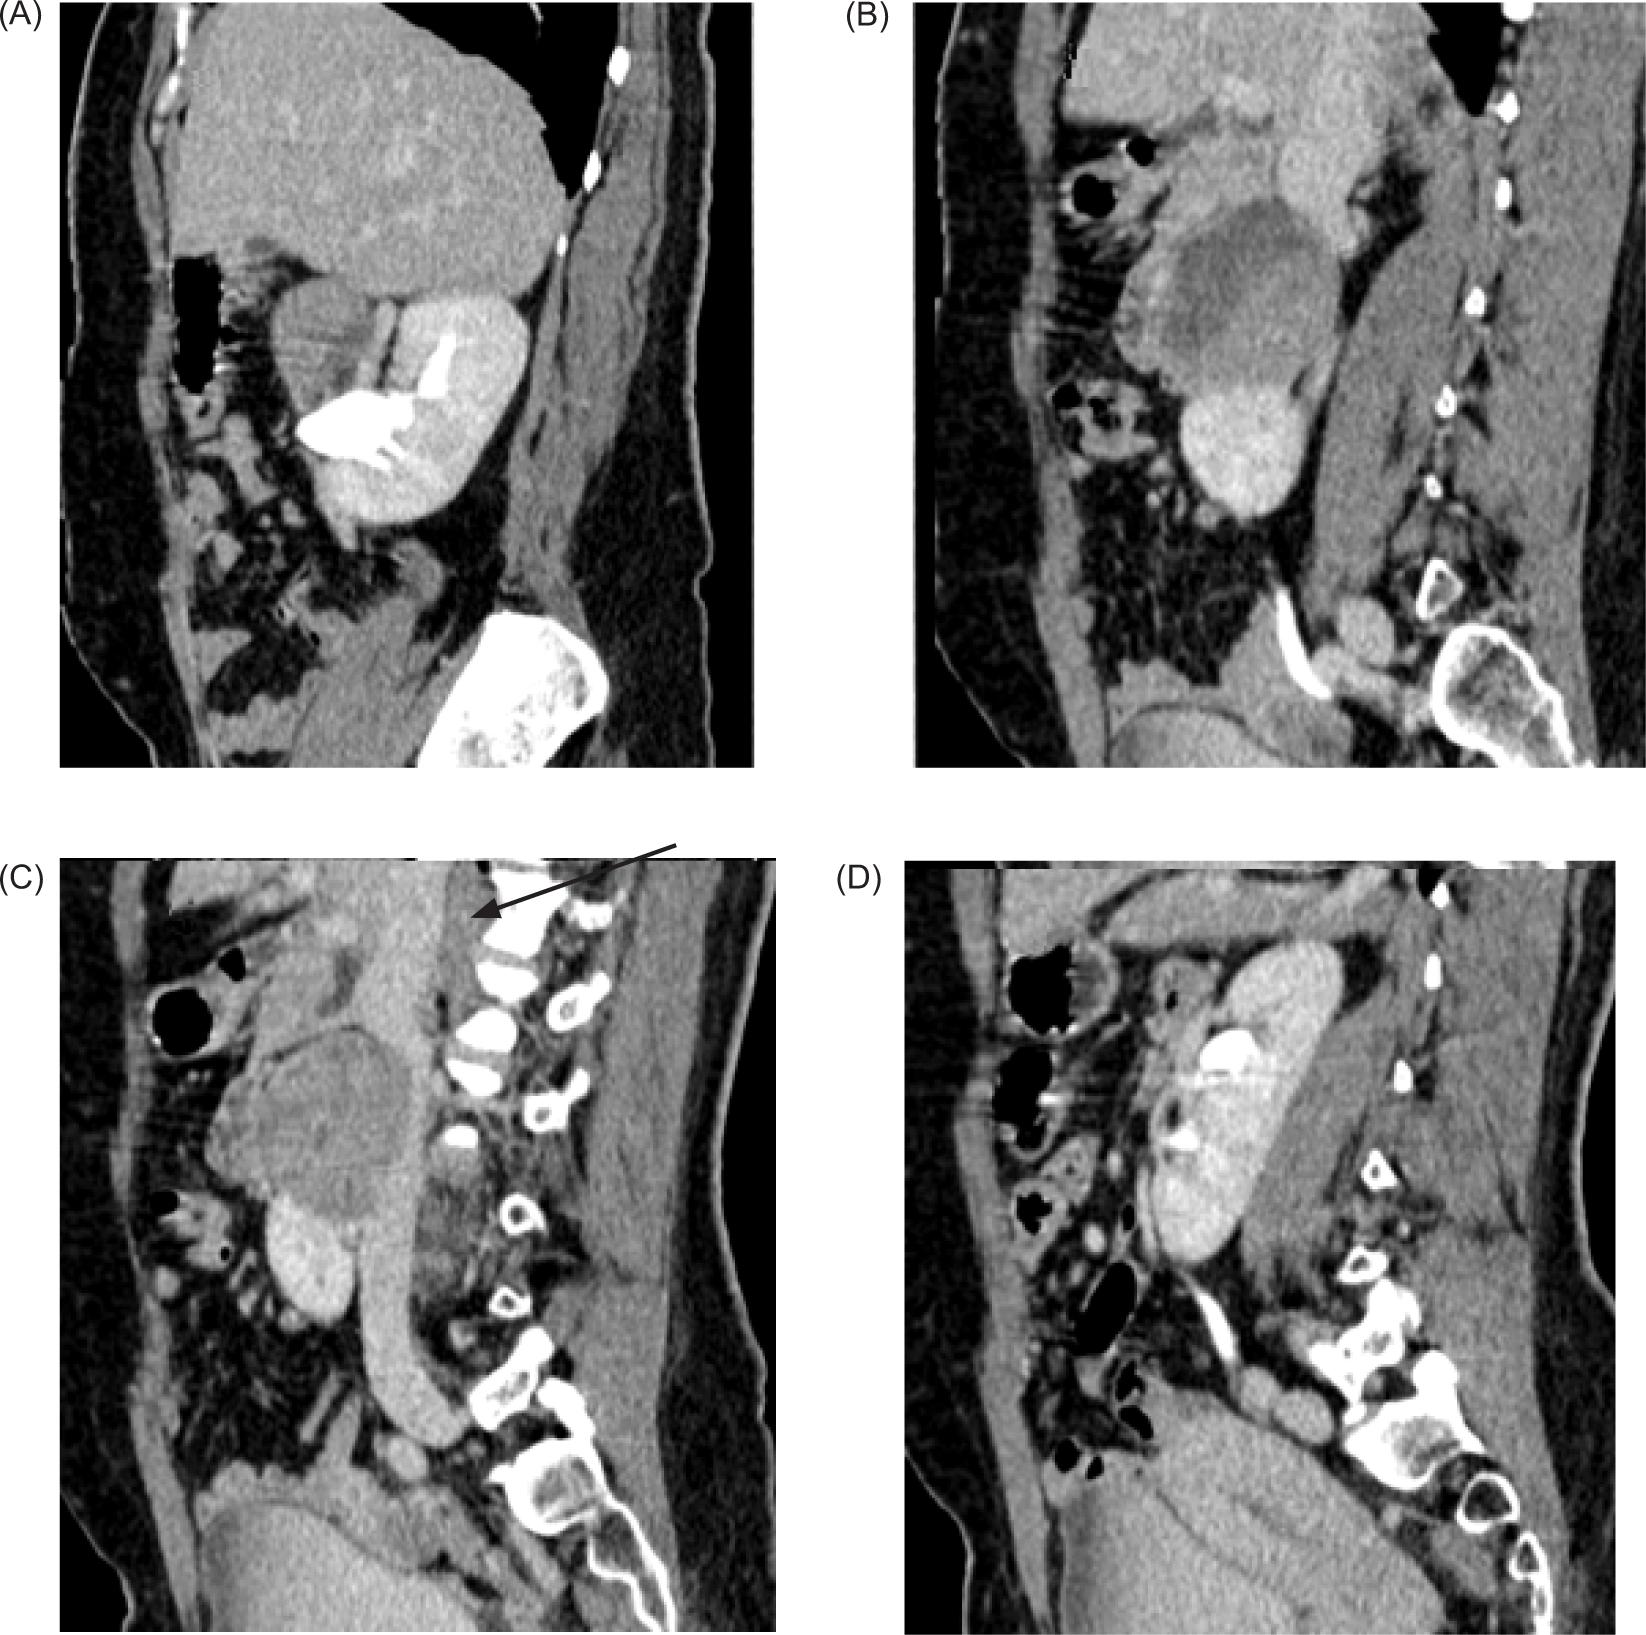

Plain and contrast-enhanced CT scan of abdomen was performed for further evaluation. It revealed HSKs with lower pole of both kidneys deviated medially and fused in midline with renal parenchyma measuring 2.1 cm in thickness and 3.3 cm in cranio-caudal extent. Calyces of lower pole of both kidneys were directed medially. Left kidney showed a bifid renal pelvis. A large, well-defined solid mass of heterogeneous density showing heterogeneous post-contrast enhancement measuring 66 x 54 x 57 mm (transverse x anteroposterior x craniocaudal, respectively) was noted arising from the superior portion of isthmus and extending superiorly at adjoining retroperitoneum and abutting medial surface of right kidney up to renal hilum with obscuration of intervening fat plane. It was extending anterior to right renal hilum and abutting anterosuperior surface of right renal pelvis (Figure 2).

Figure 2: Contrast-enhanced CT coronal sections showing medially deviated lower poles of the bilateral kidneys with heterogenous enhancing mass arising from the superior portion of isthmus of the HSK abutting the hilum of right kidney.

This mass was causing extrinsic compression and anterior displacement of distal portion of second part and proximal portion of third part of duodenum that were compressed and displaced anteriorly (Figure 3).

Figure 3: (A–D) Axial contrast enhanced CT abdomen showing well-defined heterogeneously enhancing solid mass arising from isthmus compressing and displacing adjoining second and proximal third portion of the duodenum (arrow in [A]).

The pancreatic head was compressed and displaced anteriorly; posteriorly mass effect was noted on anterior surface of inferior vena cava with obliteration of intervening fat plane. IVC as a result was compressed and flattened anteroposteriorly (Figure 4).

Figure 4: (A–D) Contrast enhanced CT sagittal images—Mass arising from the isthmus, posteriorly compressing the IVC with obliteration of intervening fat planes (arrow).